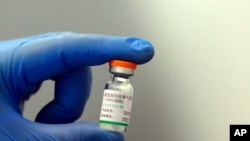

Last week Serbia received one million doses of Chinese Sinopharm's COVID-19 vaccine, becoming the first European country to start a mass inoculation program with it.

China approved the shot developed by Sinopharm's BIBP in late December, its first COVID-19 vaccine for general public use. No detailed efficacy data has been released, but BIBP has said the vaccine is 79.34% effective based on interim data.